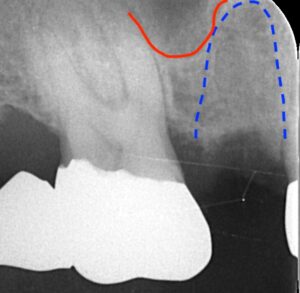

ソケットプリザベーションを終えた後です。

3ヶ月後にインプラントの埋入手術を終えたレントゲンです。

上顎洞を少し持ち上げるソケットリフトを行なっています。